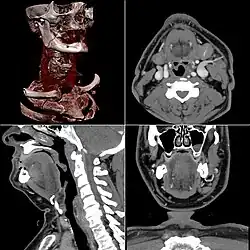

A partir de todas esas imágenes transversales (axiales), un computador reconstruye una imagen bidimensional que permite ver secciones de la pierna (o el objeto de estudio) desde cualquier ángulo. Los equipos modernos permiten incluso hacer reconstrucciones tridimensionales. Estas reconstrucciones son muy útiles en determinadas circunstancias, pero no se emplean en todos los estudios, como podría parecer. Esto es así debido a que el manejo de imágenes tridimensionales no deja de tener sus inconvenientes.

Un ejemplo de imagen tridimensional es la imagen 'real'. Como casi todos los cuerpos son opacos, la interposición de casi cualquier cuerpo entre el observador y el objeto que se desea examinar hace que la visión de este se vea obstaculizada. La representación de las imágenes tridimensionales sería inútil si no fuera posible lograr que cualquier tipo de densidad que se elija no se vea representada, con lo que determinados tejidos se comportan como transparentes. Aun así, para ver completamente un órgano determinado es necesario mirarlo desde diversos ángulos o hacer girar la imagen. Pero incluso entonces veríamos su superficie, no su interior. Para ver su interior debemos hacerlo a través de una imagen de corte asociada al volumen y aun así parte del interior no siempre sería visible. Por esa razón, en general, es más útil estudiar una a una todas las imágenes consecutivas de una secuencia de cortes que recurrir a reconstrucciones en bloque de volúmenes, aunque a primera vista sean más espectaculares.